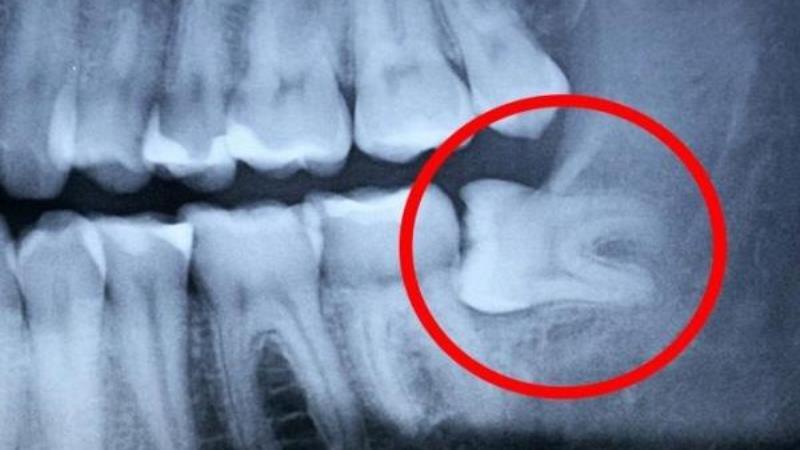

Зуб мудрости может вызывать головную боль у многих пациентов. При росте этого зуба около 30% людей сталкиваются с таким симптомом. Боль может распространяться по всей области головы, сопровождаться воспалением лимфоузлов и даже повышением температуры. Если рост зуба мудрости сопровождается этими неприятными симптомами, рекомендуется обратиться к терапевту и стоматологу. В некоторых случаях может потребоваться оперативное вмешательство для устранения воспаления, особенно если на десне образуется капюшон с воспалением и нагноением. Однако большинство болезненных ощущений связаны только с прорезыванием зуба. После того, как зуб мудрости прорезался, обычно наступает улучшение, боли утихают и температура нормализуется. Иногда стоматолог может решить удалить зуб мудрости, если он вызывает серьезный дискомфорт у пациента. Показаниями к удалению могут быть неправильное расположение и наклонение зуба, его влияние на соседние зубы, развитие воспаления или кариозного разрушения. Удаление зуба мудрости является относительно простой процедурой, но требует определенной подготовки и анестезии. У некоторых пациентов после удаления зуба мудрости может болеть ухо или височная область. Обычно неприятные ощущения проходят в течение нескольких дней, но иногда заживление может занять более недели и сопровождаться определенными симптомами. После удаления зуба мудрости рекомендуется полоскание отварами трав для снятия воспаления и обеззараживания раны. Если это не приводит к облегчению, следует обратиться к врачу для осмотра. Основными причинами боли после удаления зуба мудрости могут быть травма надкостницы и костной ткани, травматические осложнения или несоблюдение рекомендаций. Если после удаления зуба мудрости болит голова и нет осложнений или воспалений, стоматолог может назначить обезболивающие препараты. После удаления зуба рекомендуется воздержаться от еды и питья в течение двух часов, чтобы ускорить заживление и предотвратить инфекцию раны. Опытные стоматологи предпочитают удалять зуб мудрости в состоянии покоя, чтобы избежать головных болей, осложнений и отеков, которые могут возникнуть при удалении воспаленного зуба.